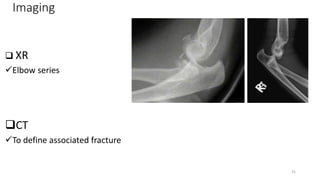

Imaging

 XR

Elbow series

CT

To define associated fracture